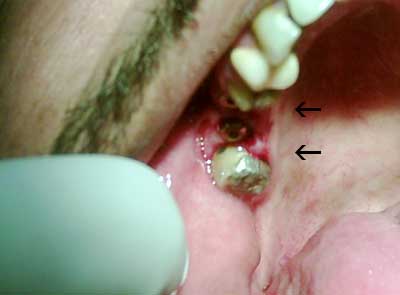

الزرعات في الفك السفلي إنظر إتجاه الأسهم